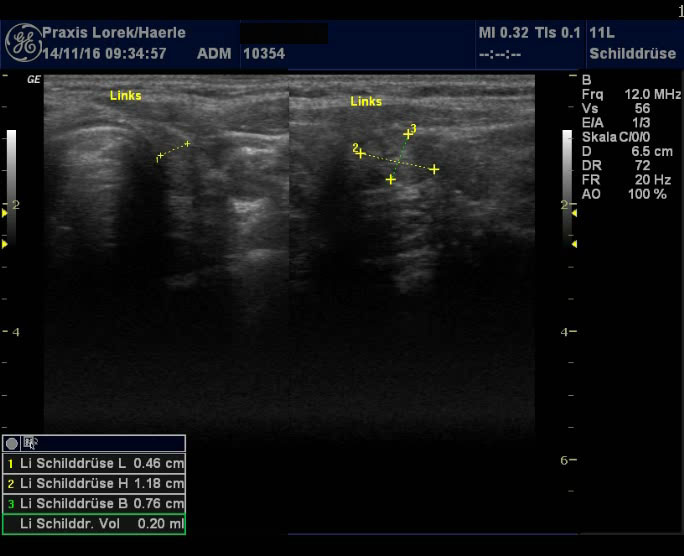

Abb. 1 und 2: Kleine

Rest-Schilddrüse bds. nach subtotaler Thyreoidektomie 1995 wegen Morbus

Basedow. Restgewebe postoperativ geringfügig gewachsen, typisches

inhomogenes Muster wie bei einer Basedow-Struma. Patientin mit

polyglandulärem Syndrom: Diabetes mellitus Typ I, Endokrine Ophthalmopathie,

Vaskulitis mit Fingerendgliedamputationen.